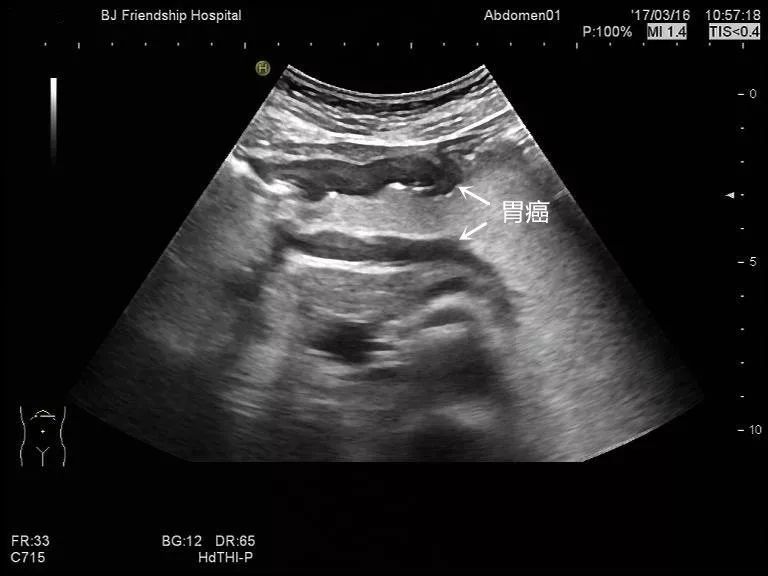

胃角部胃癌:

胃体部胃癌: